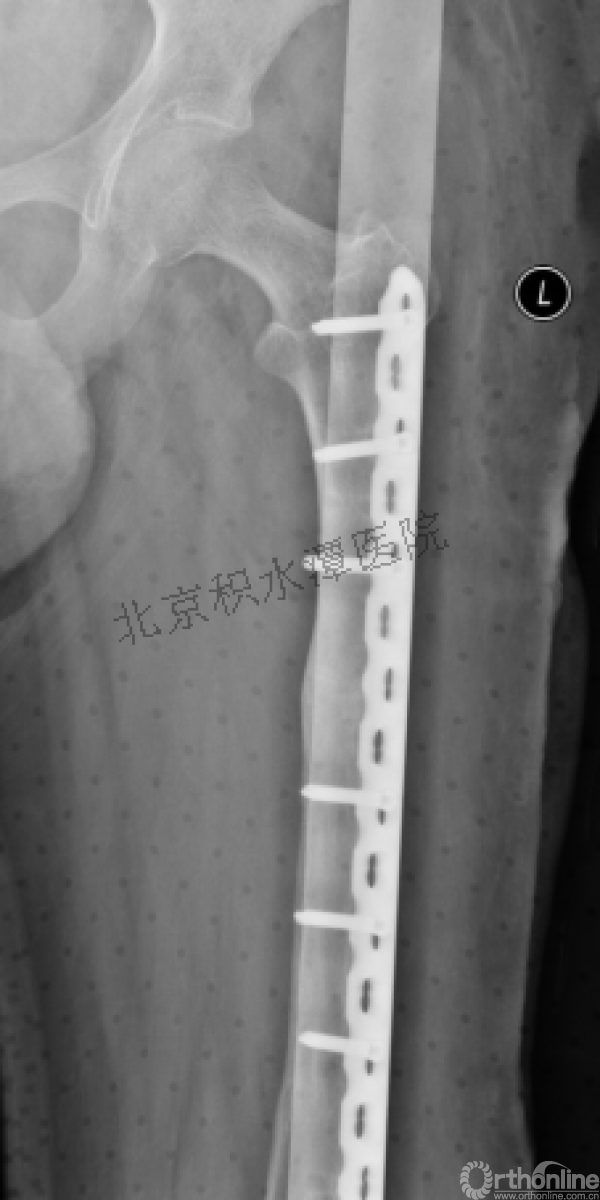

病例分享一

男孩 、5岁,初次骨折于2007年7月。

术后2年→再骨折→再次手术

钢板固定后一年

取板后再骨折→TEN

TEN取出后2个月

闭合复位再固定加尾帽

又过了4年!时间来到2015年

一年以后顺利愈合,实则危机四伏

数月后再骨折!牵引!

髋人字支具

外固定架术后一年

整整11年!是否治疗终结?

病人的付出?医生当反思!